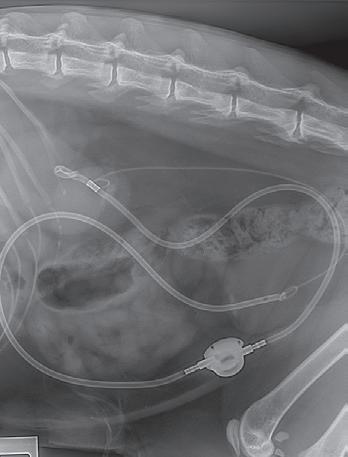

Uretral Stenting Surgery at the Centre for Animal Referral & Emergency (CARE)

Ureteral obstruction is increasingly recognised as a cause of acute renal dysfunction in cats. Fortunately, there is a range of options for renal decompression using tubing, or stents, to divert urine past the site of obstruction to external collection systems (percutaneous nephrostomy) or to the bladder, placed either within the ureter (endoluminal) or external to it (Subcutaneous Ureteral Bypass). Dr Guy Yates and the surgery team at CARE regularly perform ureteral stenting surgery and have recently published an evolution of a common stenting procedure that minimises postoperative complications and simplifies surgical placement. Many factors influence the post-operative prognosis, however, re-establishment of urine flow from the kidney preserves renal function and achieves a favourable outcome in many patients.

For enquiries or referrals contact (03) 9417 6417